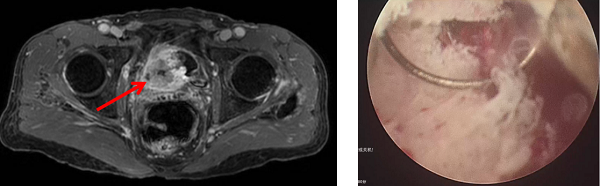

2025年11月,65歲的張先生(化名)因尿頻、尿急,來到柳州市人民醫(yī)院就醫(yī)。經(jīng)過詳細(xì)的病史詢問、查體以及必要的CT、盆腔磁共振以及膀胱鏡活檢等檢查,醫(yī)生發(fā)現(xiàn)張先生的膀胱右側(cè)壁長(zhǎng)了一個(gè)惡性腫瘤,而且腫瘤已侵犯膀胱全層,且連累到右側(cè)輸尿管口,導(dǎo)致右側(cè)腎積水。按照臨床分期,已經(jīng)為局部晚期肌層浸潤(rùn)性膀胱癌(T3-4期),情況十分危急。

術(shù)前影像可見腫瘤已侵犯膀胱全層

按照傳統(tǒng)的治療方案,張先生需接受膀胱切除術(shù),術(shù)后需終身佩戴集尿袋。為了能在治療后,仍能維持正常的生活狀態(tài),過得更有“尊嚴(yán)”,張先生向醫(yī)生表達(dá)了希望能保住膀胱的強(qiáng)烈意愿。